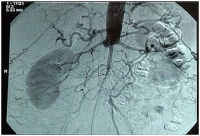

PM 303-2

Bilateral CIA occlusion; embolism in left EIA